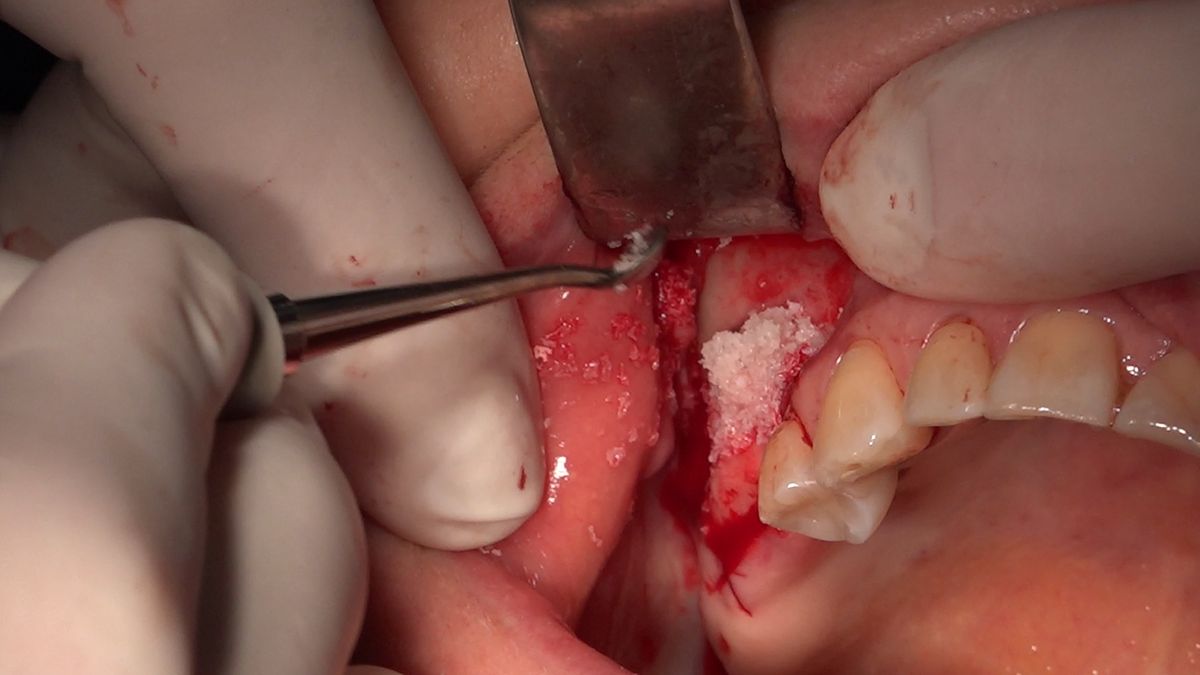

Practiculum Implantologii – Sezon VIIB, sesja 7, dzień 2